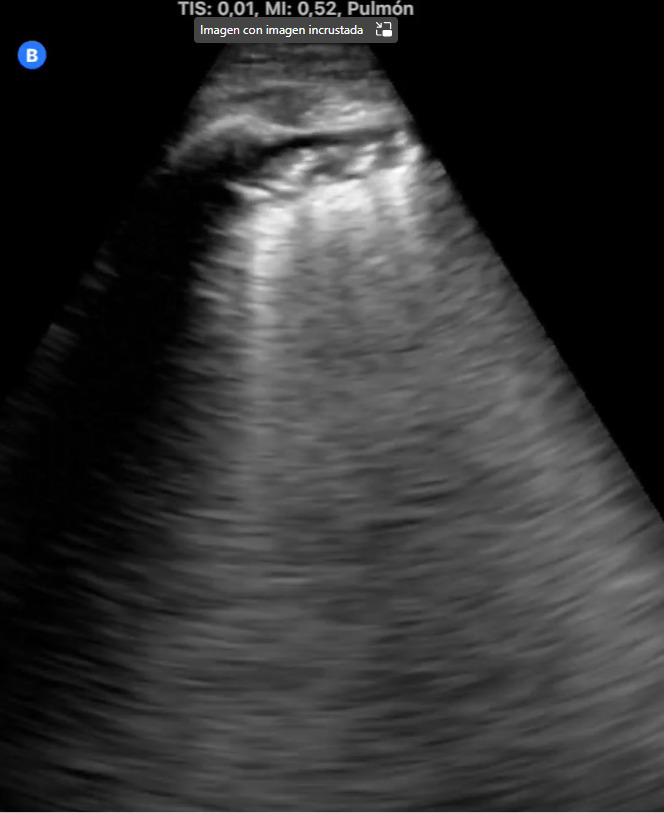

La ecografía pulmonar nos permite aumentar la capacidad diagnóstica y resolutiva, con gran rapidez y gran número de situaciones clínicas, disminuyendo el nivel de incertidumbre. Nos ayuda a tomar decisiones y ofrecer un mejor cuidado a los pacientes. Permite evaluar la extensión y gravedad de la enfermedad, así como monitorizar la progresión y evaluar las complicaciones.

Además, ayudándonos de la ecografía pulmonar, hemos podido diagnosticar diferentes patologías pulmonares intersticiales como neumonitis intersticial por metotrexate, neumopatía intersticial tipo NINE y síndrome alveolo intersticial.

La ecografía es una herramienta valiosa en la evaluación y manejo de patologías pulmonares intersticiales, proporcionando información clave que puede influir en el tratamiento y pronóstico del paciente.